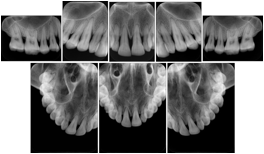

2. A patient requests cosmetic surgery to enhance their facial appearance. The case requires consultation between an orthodontist in New York and an oral surgeon in California. The cephalometric series of 2D projections constructed from a volumetric CT data set that is used for the discussion is arranged by a Structured Display for transfer between the two practitioners.

Cephalometric Series Structured Display

Figure OO-2. Cephalometric Series Structured Display